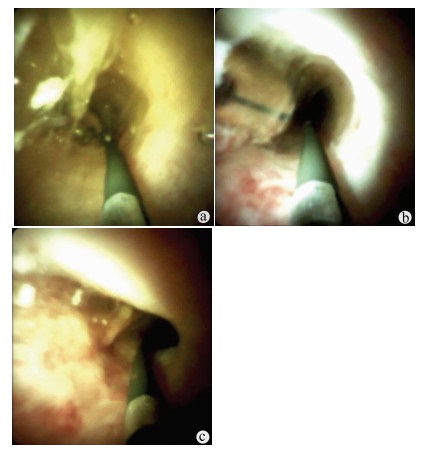

Application of transjugular liver biopsy in the diagnosis and treatment of complicated and severe liver diseases

Hua TIAN, Qiang YU, Shaoli YOU, Sa LYU, Shuhong LIU, Bing ZHU

2021, 37(12): 2874-2877. DOI: 10.3969/j.issn.1001-5256.2021.12.027

Abstract(1229) HTML (245) PDF (2586KB)(88)

Abstract:

Objective  To investigate the application value of transjugular liver biopsy (TJLB) in the diagnosis and treatment of complicated and severe liver diseases.  Methods  A retrospective analysis was performed for the clinical data of 31 patients who underwent TJLB in The Fifth Medical Center of Chinese PLA General Hospital, including indication for puncture, success rate, and final diagnosis.  Results  Among the 31 patients, there were 15 male patients and 16 female patients. Percutaneous liver biopsy was unsuitable for 8 patients with liver failure and disturbances of blood coagulation, 13 with liver cirrhosis and ascites, and 10 with liver cirrhosis and thrombocytopenia (< 50×109/L), which were the indications for TJLB. The success rate of TJLB puncture was 100%, with 2-4 passes for puncture. No serious adverse event was observed. Of all 31 patients, 26 (83.87%) had a definite diagnosis at discharge, among whom there were 5 patients with idiopathic portal hypertension, 9 patients with drug-induced liver failure or liver cirrhosis, 5 patients with autoimmune liver disease, and 7 patients with liver cirrhosis or liver failure due to other causes, and 5 patients had unknown etiology. In addition, 3 patients underwent biopsy to confirm the diagnosis and decision of whether liver transplantation should be performed.  Conclusion  TJLB plays an important role in the diagnosis and treatment of complicated and severe liver diseases and still has certain limitations, and therefore, suitable patients should be selected in clinical practice.